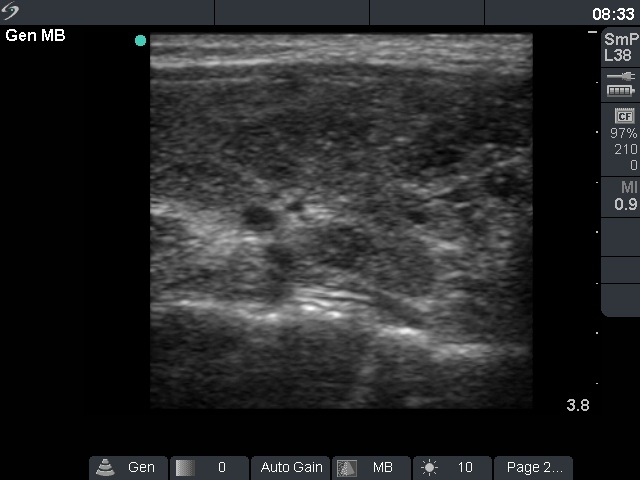

Follow-up examination 17 months after first visit (second and third rows):

Clinical presentation: The patient was well. She came to sonographic follow-up suggested at her first visit.

Palpation: a hard nodule in the upper part of the left thyroid.

Functional state: subclinical hyperthyroidism (TSH undetectable, FT4 21.1 pM/L, FT3 6.68 pM/L).

Ultrasonography: The echogenicity index of the thyroid was 50%. The vascularization was not significantly increased. There was a large hypoechogenic, inhomogeneous nodule in the upper part of the left lobe. Both the intranodular and the perinodular blood flows were increased.

2. It is worth analyzing the video recorded at the second examination. Both the nodule and the extranodular part present fibrotic changes, moreover the inhomogeneity of the extranodular part is more pronounced than that of the nodule.